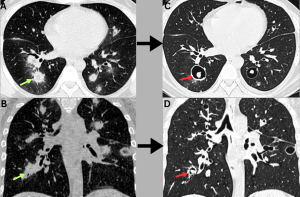

Fig 16: Clinical history:

A 48-year-old male with post-COVID mucormycosis presented with a worsening cough.

Figures A & B:

Axial and coronal HRCT chest images demonstrate multiple discrete consolidative nodules with peripheral ground-glass halos (green arrows).

Figures C & D:

Follow-up HRCT chest performed 2 months later demonstrates cavitary transformation of the lesions with dependent soft-tissue content (red arrows), indicating interval disease progression.